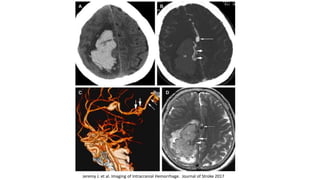

TAC: sensible para identificar sangrado RMN T2 y eco gradiente: agudo y cronico

Nancy J. Fischbeina, et al. Nontraumatic Intracranial Hemorrhage. Neuroimag Clin N Am 20 (2010) 469–492

Jeremy J. et al. Imaging of Intracranial Hemorrhage. Journal of Stroke 2017

Scott D. Smith et al, Hemorrhagic Stroke. Radiol Clin N Am 49 (2011) 27–45